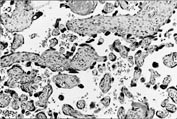

Kliniske symptomer på preeklampsi er trolig sekundære til iskemi i placenta (1, 21). Placentavevet blir skadet av redusert placentaperfusjon med lokal hypoksi og frigiving av toksiske substanser som resultat (1, 70, 71). Den såkalte akutte aterose er kjennetegnet ved forandringer i basal- og spiralarteriene, med endotelskade, trombocyttdeponering, murale tromber og fibrinoid nekrose i karveggen (fig 4). I det ekstracellulære rom deponeres fibrin, immunglobuliner og komplementfaktorer. Dette kan gi redusert blodstrøm og hypoksi (lokal eller diffus) i placenta (5, 6, 21, 72).

Ingen placentalesjon er spesifikk for preeklampsi, men fortykkelse av trofoblastbasalmembranen, infarkter og retroplacentære hematomer er hyppigere enn hos friske. Syncytiotrofoblast kan nekrotisere og cytotrofoblast proliferere som svar på hypoksi. Ved elektronmikroskopi kan det påvises fokal nekrose i syncytiotrofoblast hos gravide med preeklampsi. Ved preeklampsi er både syncytiotrofoblastantallet og antallet mikrovilli på overflaten av hver enkelt celle redusert. Hypoksi resulterer i proliferasjon av cytotrofoblast, noe som kan representere en kompensatorisk reparasjon (73 – 75). ”Syncytial knotting” (”syncytieknuter”) har vært betraktet som patognomonisk for preeklampsi (fig 5), men dette fenomenet er sannsynligvis uspesifikt (72).